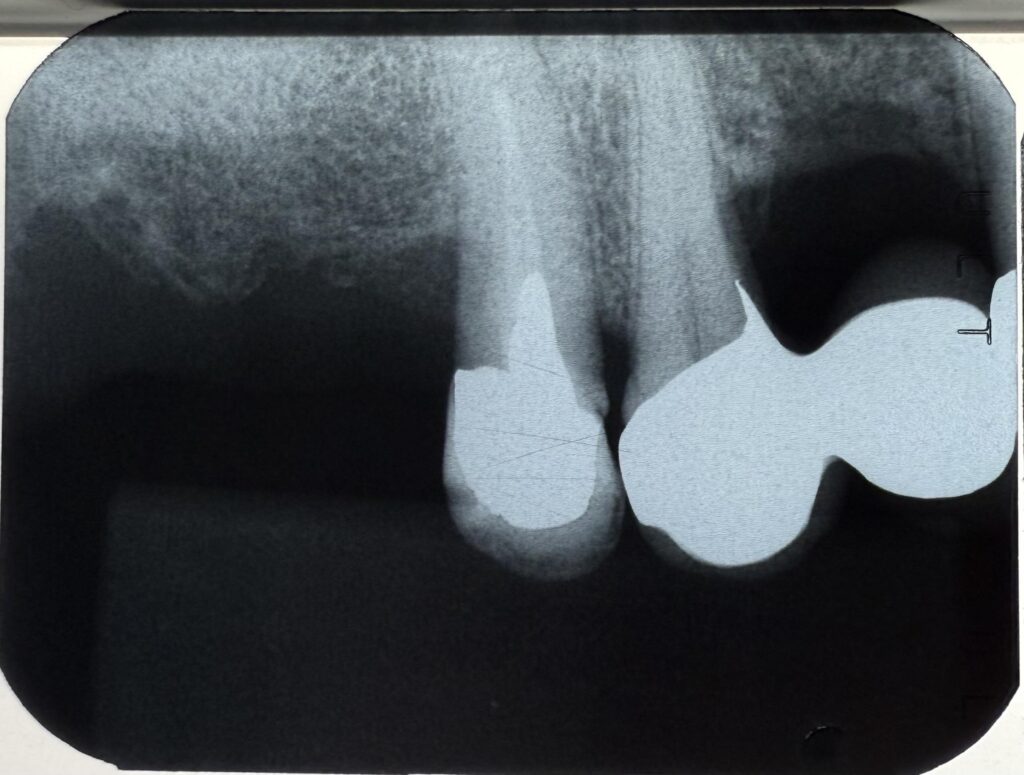

・レントゲンでの骨吸収の比較

とくにレントゲン比較は非常に重要で、初期と現在を見比べることで微細な変化を早期に発見できます。

その結果、骨の吸収も minimal で、インプラント体(フィクスチャー)は20年経っても非常に安定しています。